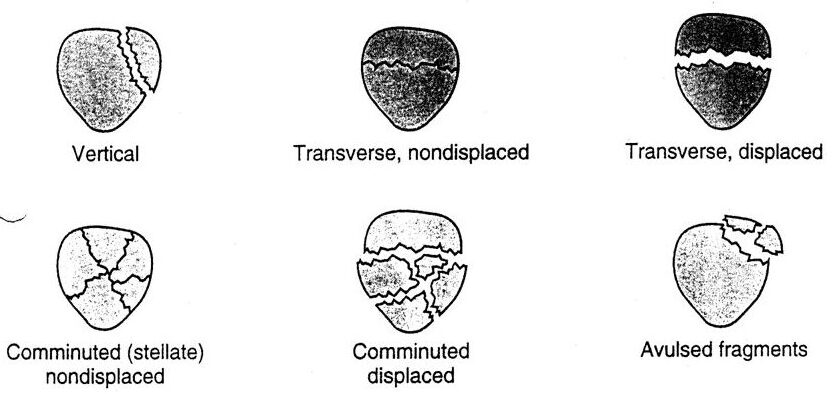

– Hai đầu xương được giữ lại với nhau bằng các dây chằng, ở hai bên là dây chằng trong và dây chằng ngoài, ở trung tâm khớp là dây chằng chéo trước và dây chằng chéo sau. Xương bánh chè là một xương vừng, nó nằm ở dưới gân cơ tứ đầu đùi và có vai trò bảo vệ gân tứ đầu cũng như tăng cánh tay đòn của gân này.